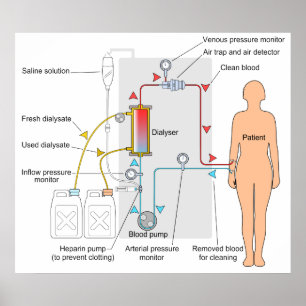

Diagram of a Haemodialysis Medical Treatment Poster

PriceCA$93.55